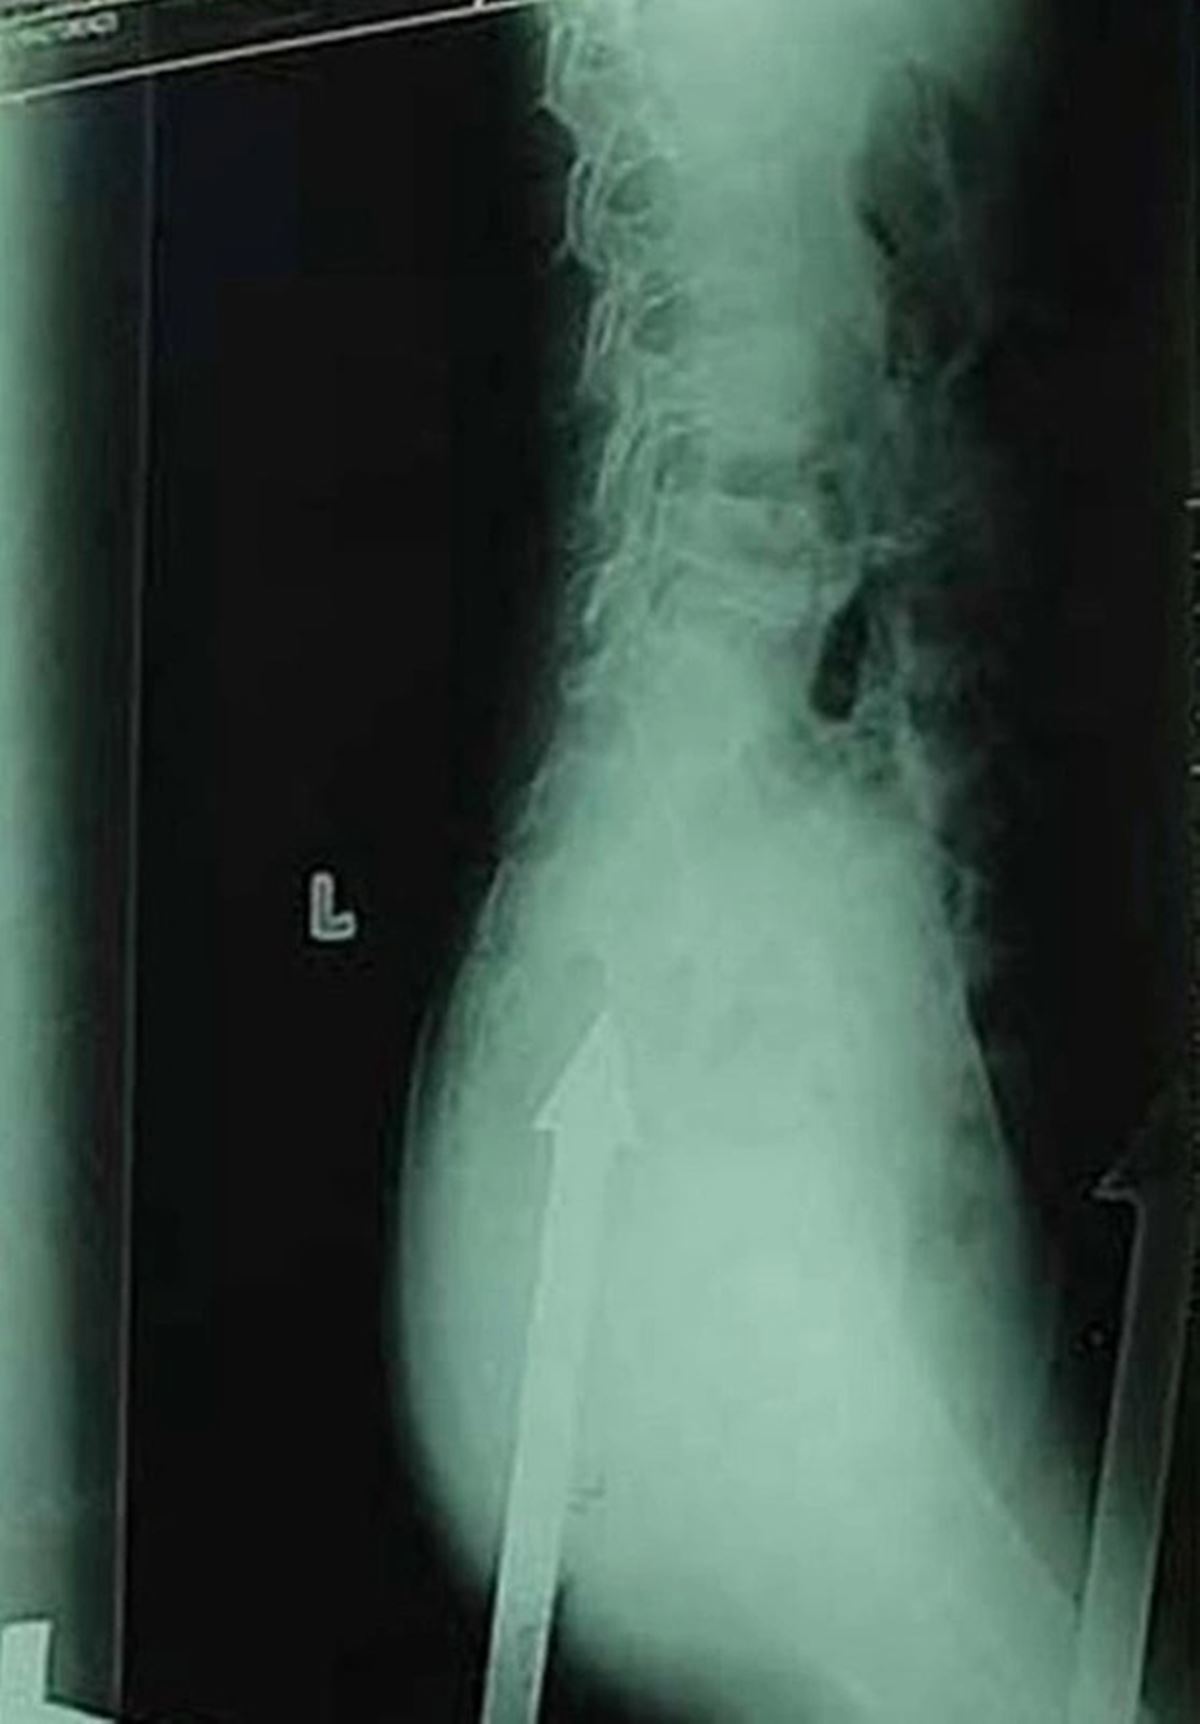

HASTANEYE ÇIKARMAK ZORUNDA KALDILAR

Kurtarıcıların 15 cm içine yerleştirilmiş direği çitin geri kalanından görmek zorunda kaldıklarını ve metal hala içerideyken çocuğu hastaneye gönderdiklerini açıkladı. 10 kadar polis memurunun olay yerinde olduğu öğrenilen gencin annesinin olay sırasında dışarıda olduğu öğrenildi.

HASTANEDE ÇIKARILDI

China Press, onu direkten çıkarma operasyonunun, çiviyi çıkarmak için ameliyat olduğu hastaneye götürülmeden önce tam 20 dakika sürdüğünü bildirdi. Ancak çocuğun son sağlık durumu hakkında bilgi verilmedi.